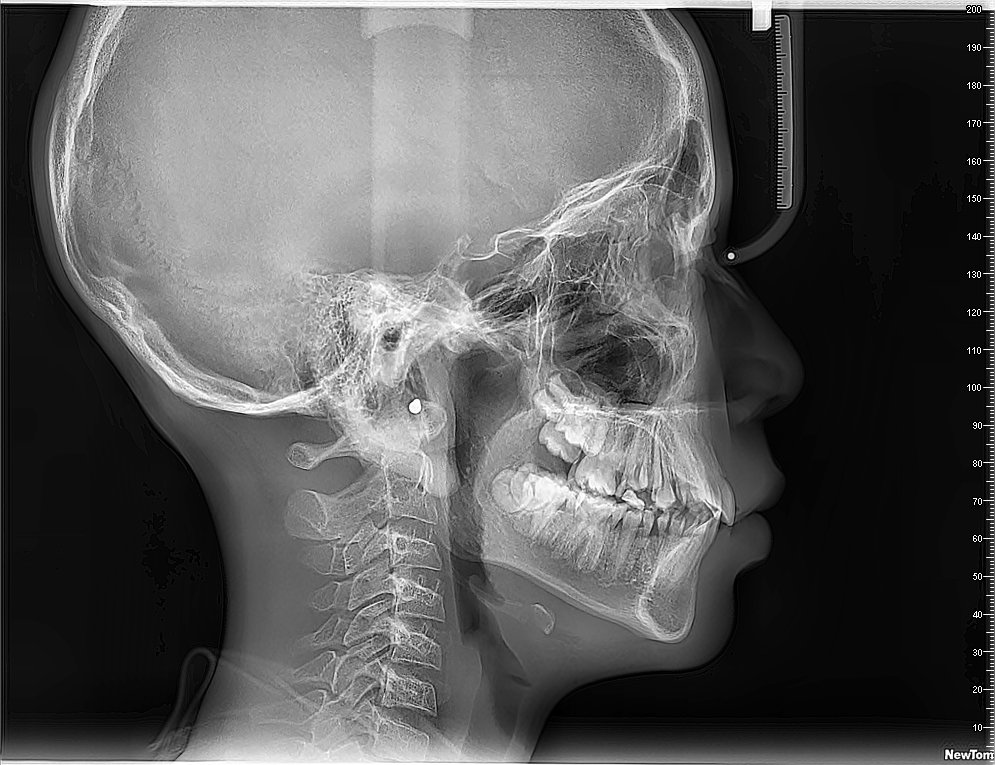

Imágenes 2D-3D Radiografías, Tomografías DENTAL, ATM, SPN, OIDO

Nuestra tecnología Cone Beam 3D permite visualizar estructuras óseas y dentales con alta definición, favoreciendo diagnósticos exactos y resultados clínicos confiables.